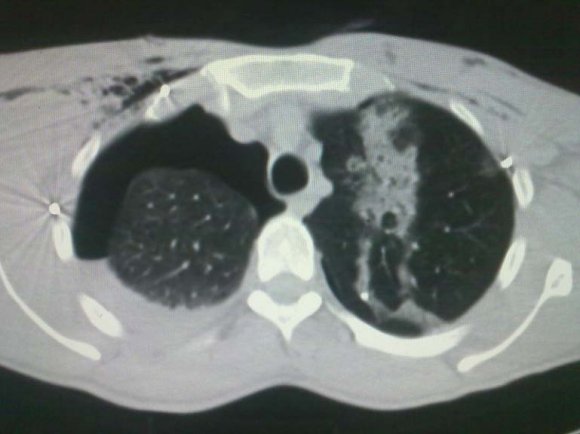

The life threatening injuries incurred in penetrating trauma are distinctly different from those of blunt injuries. Penetrating thoracic injuries (e.g., stab wounds, gunshot wounds, and impalement on a foreign body) primarily injure the peripheral lung, producing both a hemothorax and pneumothorax. More than 80% of all penetrating chest wounds cause a hemothorax, and nearly all cause a pneumothorax. The Penetrating injuries that enter or traverse the mediastinum must also be evaluated for potential cardiac, great vessel, or esophageal injury. Hemodynamically unstable patients with mediastinal entering or traversing wounds should be considered to have exsanguinating thoracic hemorrhage, pericardial tamponade, or tension pneumothorax.

Hypovolemia from intrathoracic hemorrhage is second only to rib fractures as a sequel of thoracic trauma. Penetrating injuries resulting in direct cardiac injury and pericardial tamponade can rapidly compromise cardiac function.